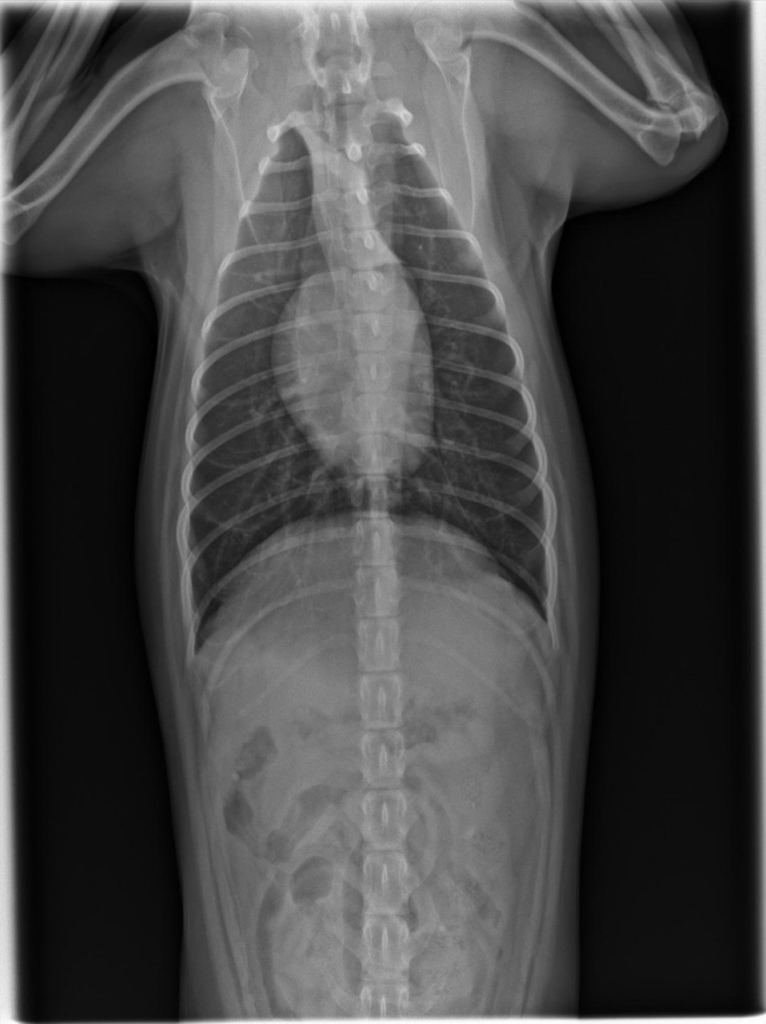

강아지가 목줄을 하고 산책 중에 갑자기 집에 가려고 차도로 뛰어드는바람에 교통사고가 났습니다. 천천히 달려오는 차에 부딪히기는 했지만 걱정돼서 바로 병원으로 갔고 엑스레이, 초음파, 혈액검사 다 시행했지만 이상이 없다고 얘기했습니다. 그런데 사고 이후로 계속 토를 해서 병원에 가서 구토약이랑 진통제를 받아와서 먹였는데도 계속 구토를 하네요ㅠ 사료를 그대로 토하는데 이게 스트레스때문인지 아니면 검사상에 이상이 있는지 여쭤보고 싶어서 글 남깁니다. 또한 가슴쪽을 부딪혔는데 흉부 엑스레이 상에서 이상소견이 있는지 확인 좀 부탁드립니다.

흉부 엑스레이상에서는 교통사고와 관련한 특별한 이상이 관찰되지 않습니다.